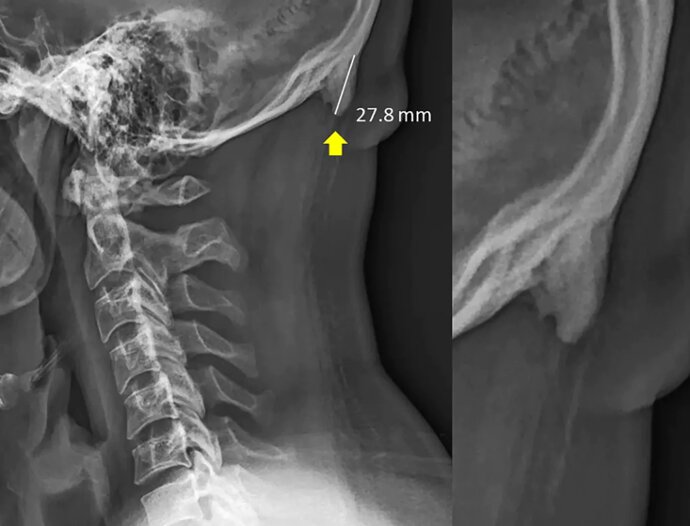

So, according to scientists, children who spend a lot of time with mobile devices can literally have a “horn”. Occipital tubercle, located under the base of the skull, in some cases reaches several centimeters in length and becomes well discernible.